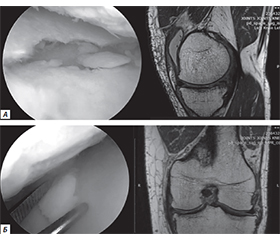

Актуальність. Фізична підготовка військовослужбовців відіграє ключову роль у забезпеченні ефективного виконання службових обов’язків, підвищення боєздатності підрозділів і збереження здоров’я особового складу. В умовах інтенсивної експлуатації організму під час бойових завдань, маршів, тактичних пересувань та тренувальних навантажень зростає ризик виникнення травм, зокрема опорно-рухового апарату. Особливо вразливими залишаються колінні суглоби, які зазнають значних динамічних навантажень. Незважаючи на відсутність впливу вогнепальних факторів, саме невогнепальні пошкодження часто призводять до тривалого лікування, втрати функціональності й тимчасової непридатності до служби. Мета дослідження: оцінити структуру, особливості й основні причини невогнепальних травм колінного суглоба у військовослужбовців Збройних сил України (ЗСУ) і проаналізувати вплив факторів ризику на їх виникнення. Матеріали та методи. У дослідженні проаналізовано результати обстежень магнітно-резонансної томографії та артроскопічних ревізій колінних суглобів 83 військовослужбовців-чоловіків віком 35–59 років (середній вік — 45,31 ± 7,48 року), які отримували лікування у відділенні важкої поліструктурної травми ДУ «Інститут травматології та ортопедії НАМН України» (м. Київ) у 2023–2025 рр. Результати. Отримані результати засвідчили переважання пошкоджень менісків (61 %), що, ймовірно, пов’язано з частими ротаційними навантаженнями та присіданнями у бойовому спорядженні. Розтягнення та розриви зв’язок становили 14 %, контузійні переломи, тріщини та хондральні пошкодження — 17 %, а хронічні дегенеративні зміни й запальні процеси — 8 % військовослужбовців ЗСУ. Висновки. Невогнепальні травми колінного суглоба становлять значну частку пошкоджень у військовослужбовців ЗСУ. Їх частота зумовлена високими фізичними навантаженнями, обмеженістю часу на адаптацію в умовах бойової обстановки та недосконалістю профілактичних заходів. Значне посилення уваги до профілактики, впровадження адаптованих тренувальних програм і своєчасна діагностика з ефективною реабілітацією здатні значно знизити ризики втрати працездатності.

Background. Physical fitness plays a crucial role in ensuring the adequate performance of military duties, enhancing the combat capability of units, and maintaining the health of service members. Under conditions of intensive physical exertion during combat missions, marches, tactical movements, and training, the risk of musculoskeletal injuries significantly increases. The knee joints are particularly vulnerable due to the high dynamic loads they endure. Although not caused by firearms, non-combat injuries often lead to prolonged treatment, functional impairment, and temporary unfitness for duty. The purpose was to assess the structure, characteristics, and primary causes of non-combat-related knee joint injuries among servicemen of the Armed Forces of Ukraine (AFU), and to analyse contributing risk factors. Materials and methods. This study analysed MRI scans and arthroscopic findings from surgical knee revisions in 83 male AFU servicemen aged 35–59 years (mean age — 45.31 ± 7.48 years), who received treatment at the Department of Severe Multistructural Trauma, SI “Institute of Traumatology and Orthopaedics of the NAMS of Ukraine” (Kyiv) in 2023–2025. Results. The data revealed a predominance of meniscal injuries (61 %), likely associated with frequent rotational loads and squatting in full tactical gear. Ligament sprains and ruptures accounted for 14 %, contusion fractures, fissures, and chondral damage for 17 %, while chronic degenerative and inflammatory joint changes made up 8 %. Conclusion. Non-combat knee injuries represent a significant proportion of musculoskeletal trauma among AFU personnel. Their prevalence is linked to intense physical exertion, limited adaptation time under combat conditions, and the lack of comprehensive preventive strategies. Strengthening prevention efforts, implementing adapted training protocols, and ensuring timely diagnosis and rehabilitation can significantly reduce the risk of disability and facilitate faster return to duty.